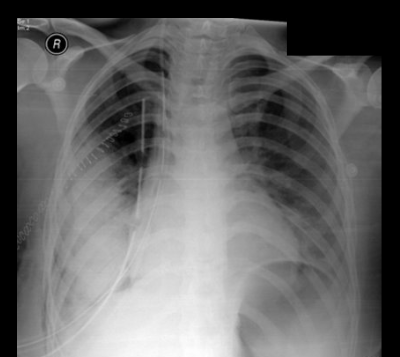

what type of tube is this?

chest tube